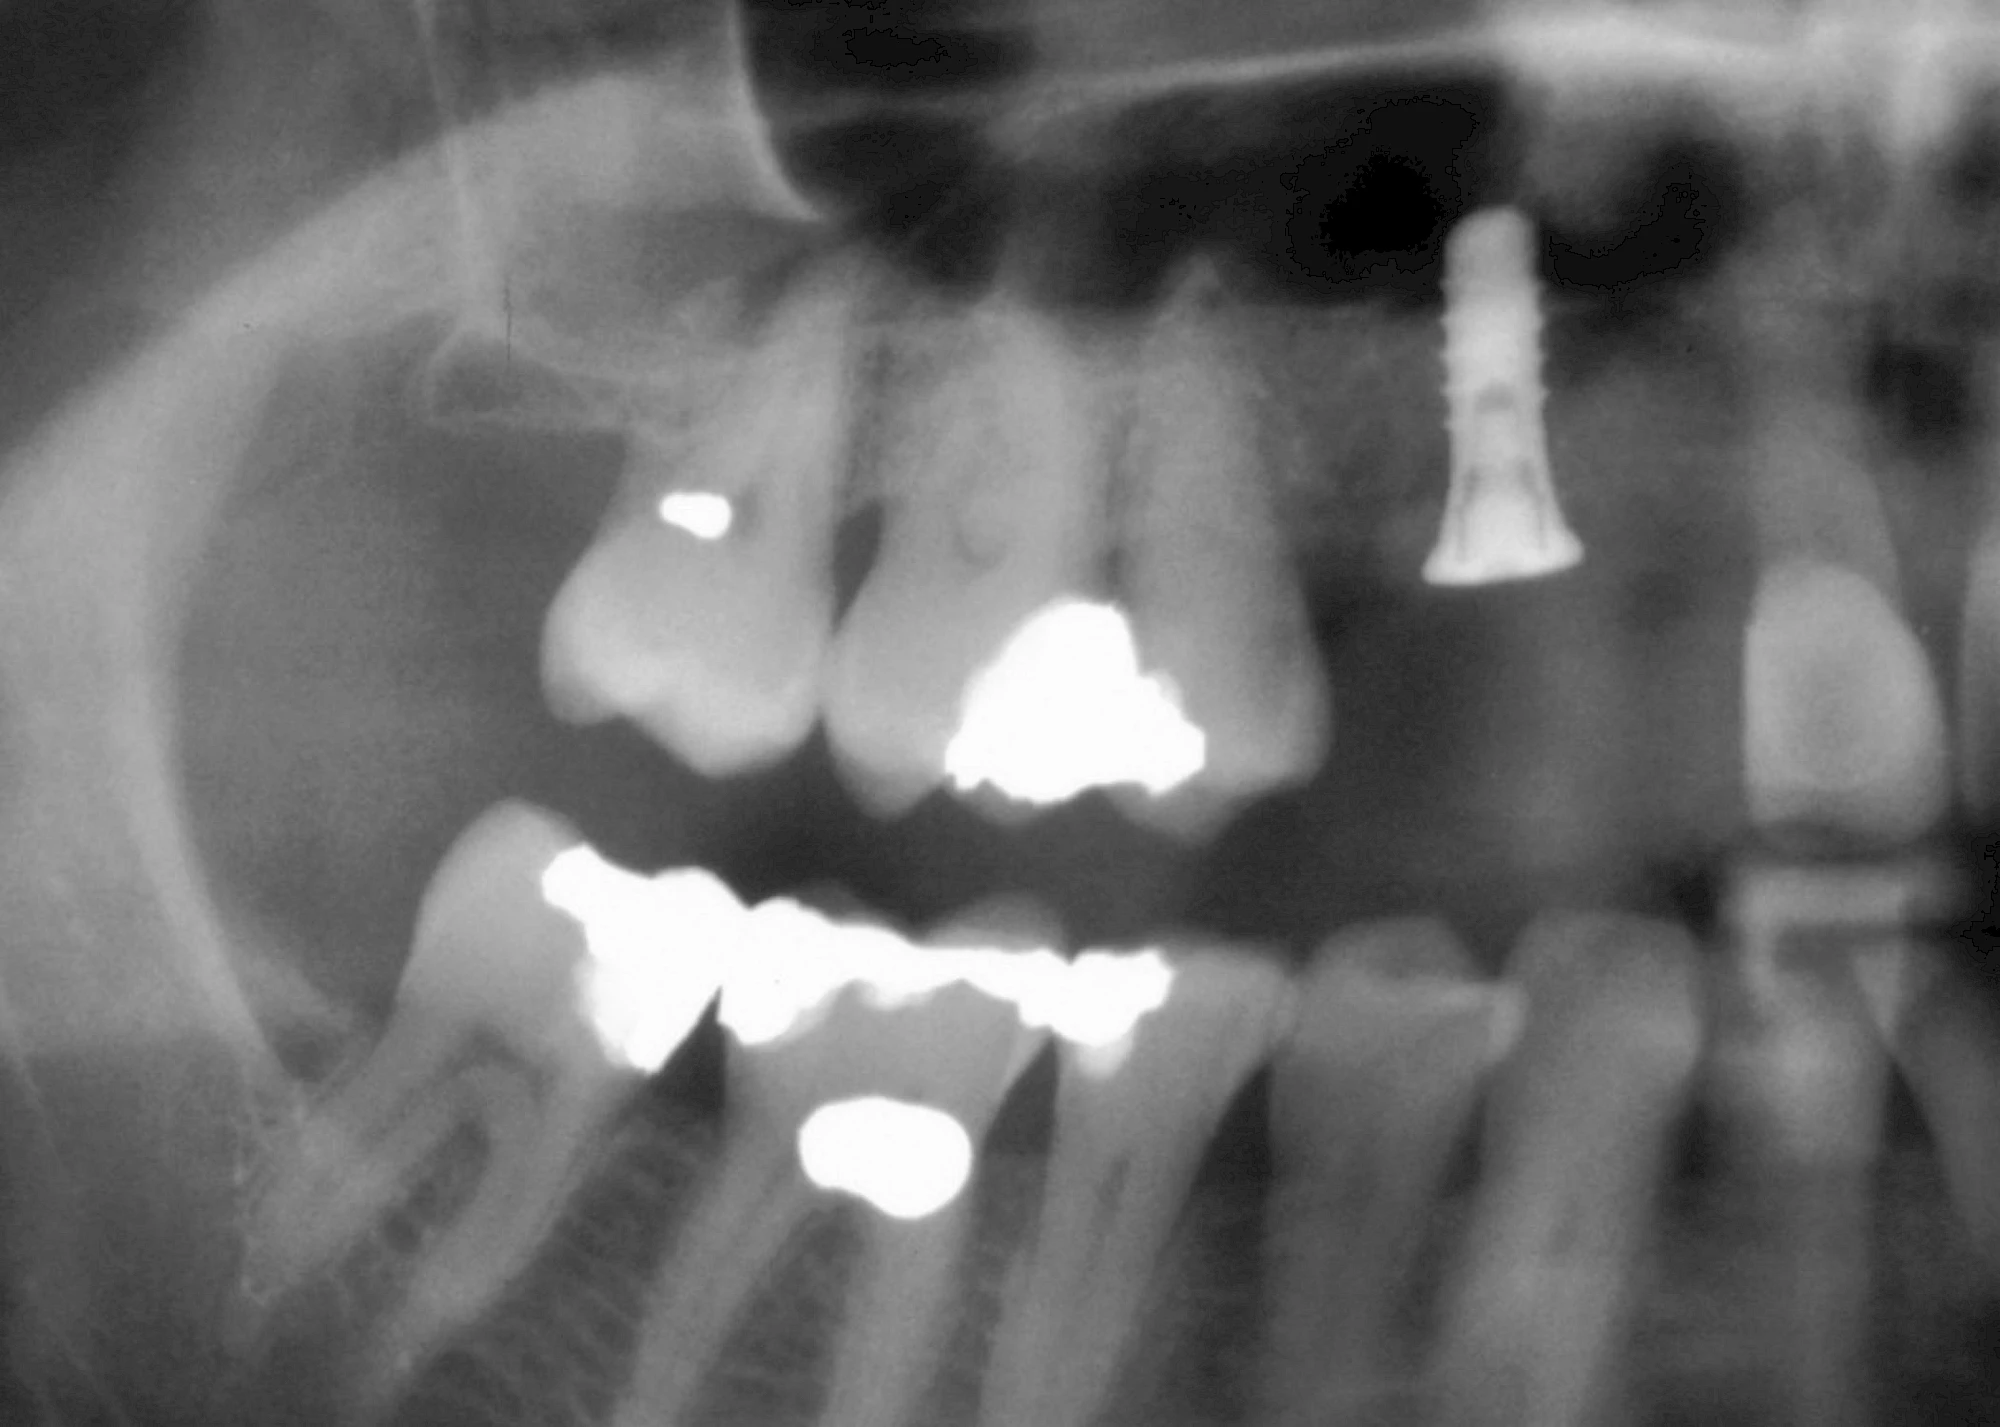

Damit Implantate an der richtigen Stelle im Kieferknochen platziert werden könen, gibt es heute vielfältige Möglichkeiten der Planung. In vielen Situationen kann die Erfahrung des Zahnarztes ausreichend sein.

Nicht selten ist jedoch auch eine technisch aufwändigere Vermessung im Vorfeld sinnvoll, z. B.:

- Wenn sich der Kieferknochen abgebaut hat

- Wenn der Nervverlauf im Unterkiefer beachtet werden muss

- Wenn die Ausdehung der Kieferhöhle im Oberkiefer beachtet werden muss

- Wenn wenige Restzähne keine gute Orientierung erlauben

In diesen Fällen kann die Planung mittels verschieden aufwendiger Röntgen-Techniken (Übersichtsaufnahme, DVT) ggf. unter Zuhilfenahme speziell angefertigter Planungsschablonen sinnvoll sein.